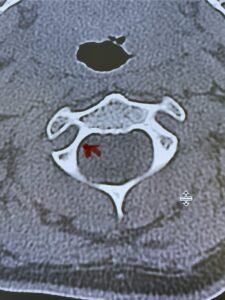

Fig. 6c: Axial cervical CT scan demonstrating a very thin right C2 isthmus (red arrow) compared to left side.